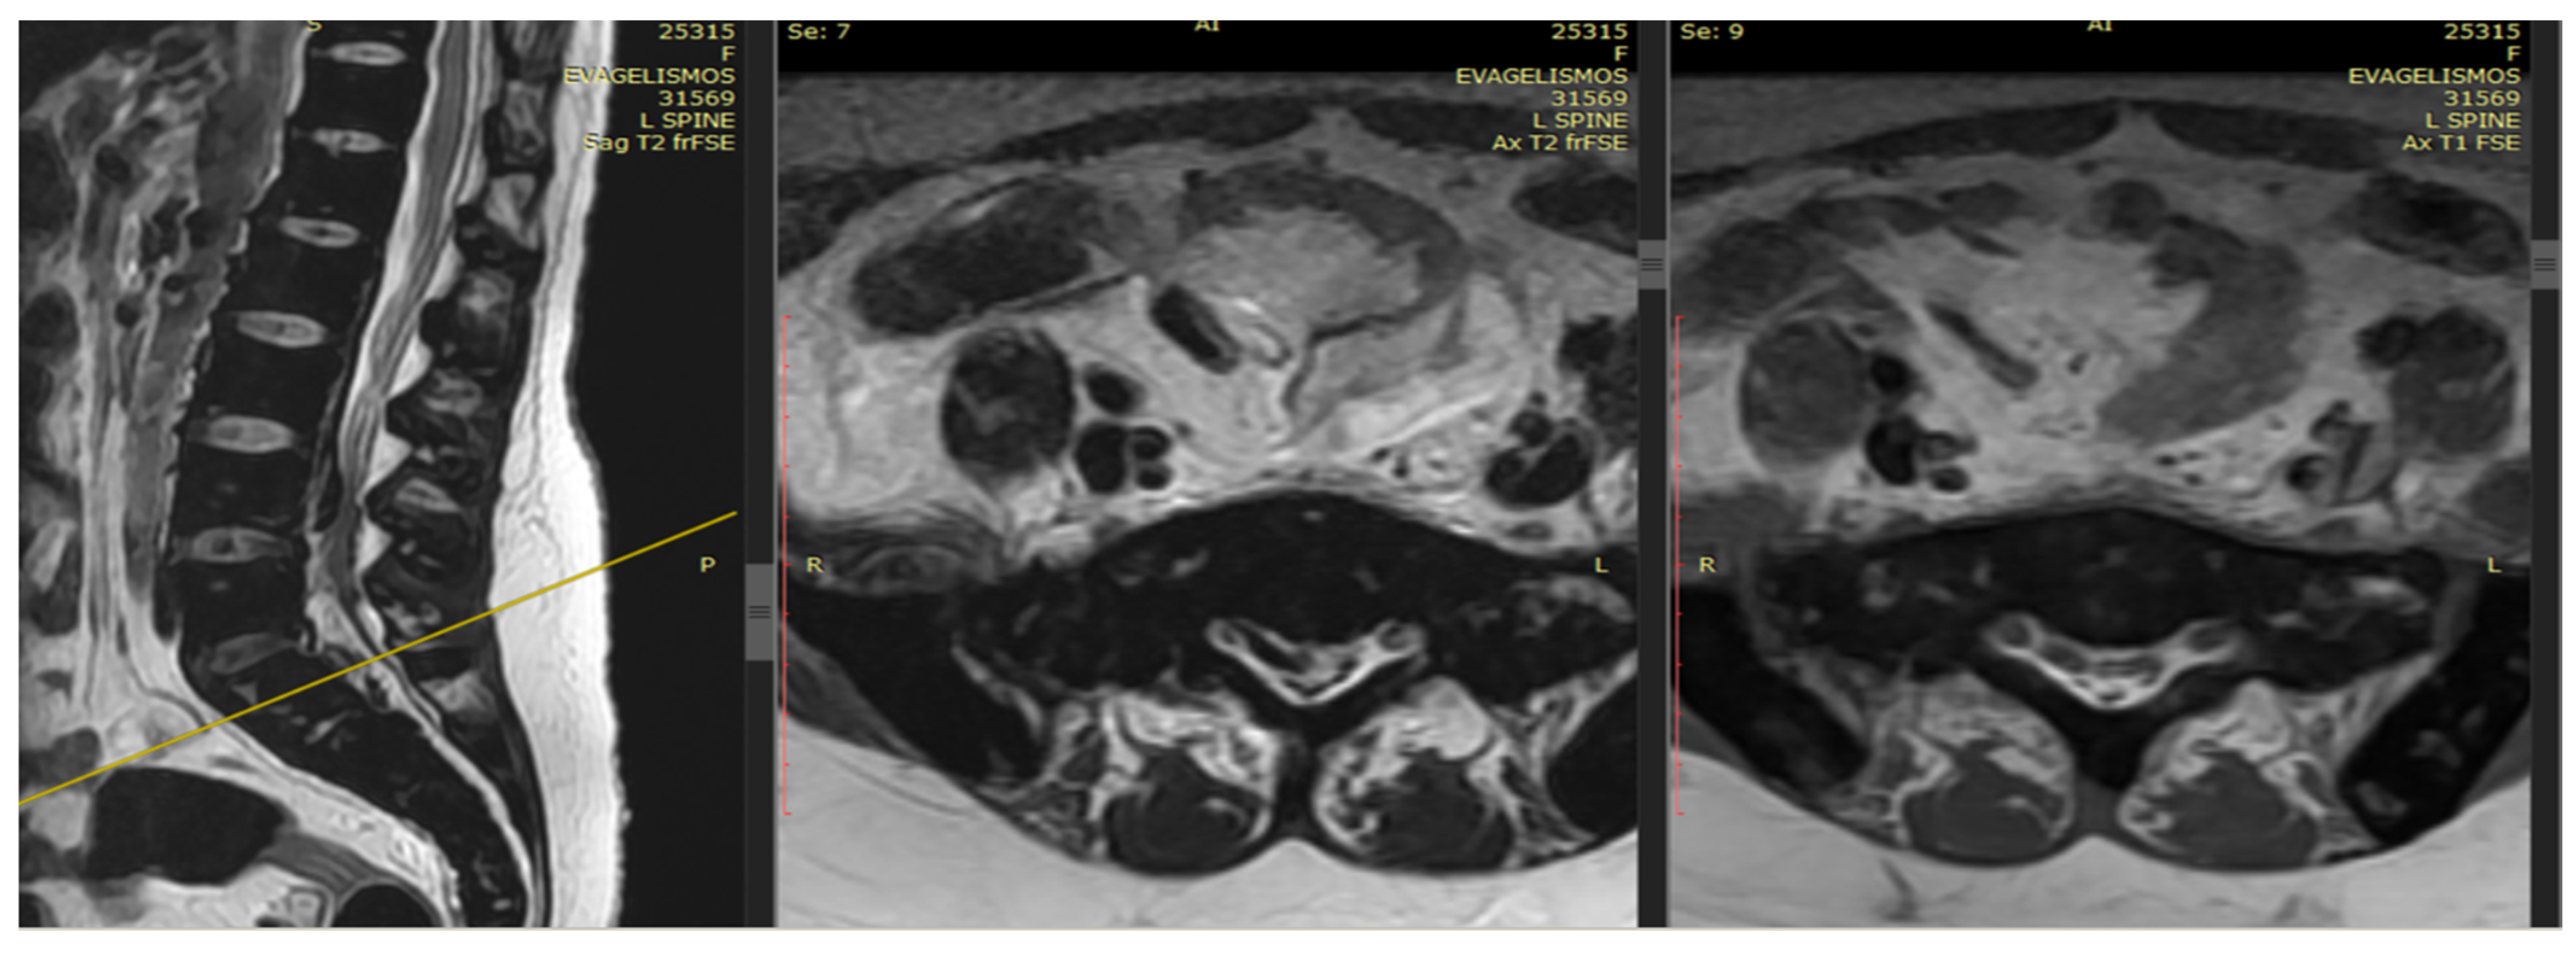

An emergency MRI was conducted on the patient, and the findings can be succinctly summarized as follows. In the T2 sequence, a low signal is observed in the anterior epidural space, accompanied by an uneven signal in the T1 sequence. These observations indicate compressive effects on the dura at the level of L2, extending towards the posterior segments of the spinal canal up to the final segment. Furthermore, a portion of this compression appears to extend along the midline fissures on the right side, particularly at the levels of L5–S1 and S1–S2, causing mild compressive effects on the nerve roots. In the GRE sequence, a low signal is noted in a segment of the aforementioned distribution, raising strong suspicion of hemosiderin deposition (Figure 1 and Figure 2). In the fat-suppressed T2 sequence, there is a diffuse increase in signal, signifying edema, in the soft tissues at the level of the midline fissures in the posterior elements and the soft tissues between the ligamentum flavum and the dura at the intervertebral foramina level. Additionally, edema is observed in the epidural space.

Figure 2.

In the T2 sequence, there is a low signal in the anterior epidural space, along with an inhomogeneous signal in the T1 sequence. These findings suggest compressive effects on the dura at the level of L2, extending to the posterior parts of the spinal canal until the final segment. Additionally, a segment of this compression seems to extend along the course of the midline fissures on the right side, specifically at the levels of L5-S1 and S1-S2, causing mild compressive effects on the nerve roots.